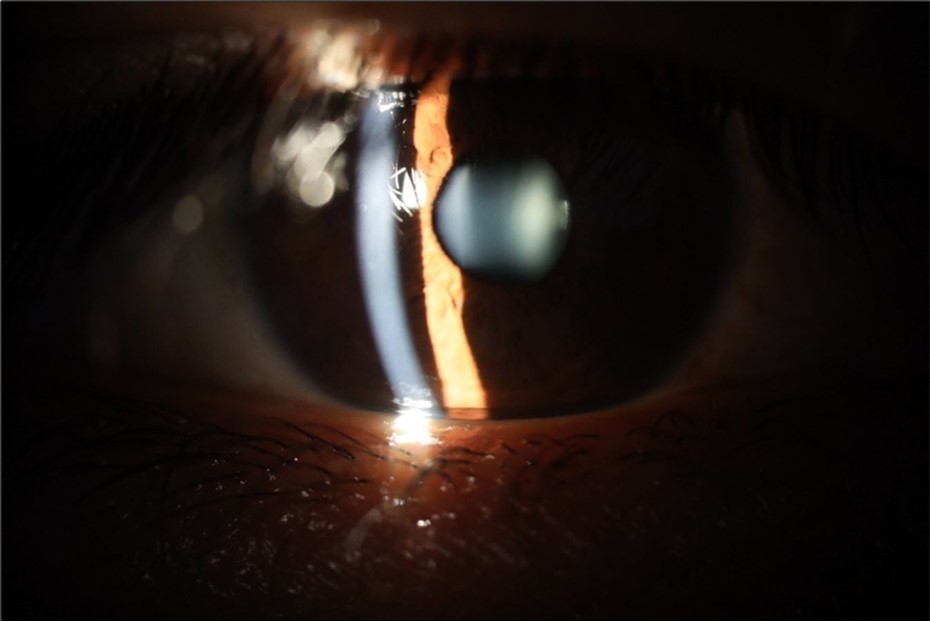

August 26, 2025

It's been fine, there's only a little veil that prevents it from seeing well completely, although it's very transparent (Figure 31, Figure 32, Figure 33, Figure 34, Figure 35, Figure 36).

Figure 35.The anatomy of the anterior segment of the left eye is shown without alterations.

The anatomy of the anterior segment of the left eye is shown without alterations.

Figure 36.The retina, optic nerve, choroid, and macula of the left eye do not show any evidence of sympathetic ophthalmia.

The retina, optic nerve, choroid, and macula of the left eye do not show any evidence of sympathetic ophthalmia.